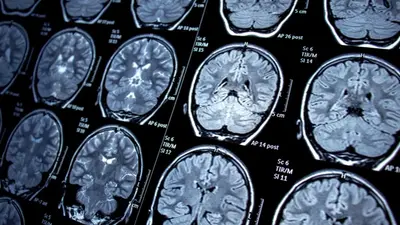

A strange and deeply concerning medical mystery has emerged at Newton-Wellesley Hospital, where 10 nurses diagnosed with brain tumors working on the same hospital ward have raised alarming questions about potential health hazards.

The affected nurses, all of whom have worked in the maternal care ward, are now seeking answers as fears grow about their safety and well-being. While some of the tumors are cancerous and others are not, the sheer number of cases concentrated in one department has led to mounting anxiety among hospital staff.

While the hospital maintains that there are no environmental risks, the affected nurses and their colleagues are left with many unanswered questions. Brain tumors are relatively rare, and the concentration of cases within one hospital ward raises concerns that go beyond mere coincidence.